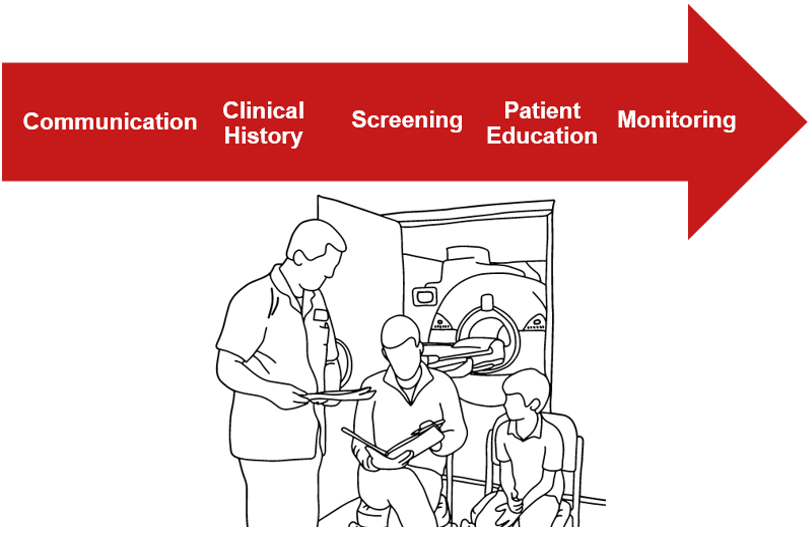

Patient care is the most important component of any CT examination. This includes communication with the patient, the procedures that are completed prior to starting an exam, during the exam and finally following the CT examination. Since many CT studies include the injection of contrast media, it also covers how to accomplish the venipuncture and injection and the signs and symptoms to look for if there is an allergic reaction of any type during the contrast injection. We will begin by reviewing why communication is so important when doing a CT scan. Also, we will discuss how radiation interacts with matter, the attenuation principle and its relation with the Hounsfield units of various tissues. We will also look at how we measure doses and methods of reducing patient doses in CT scanning. This article is accredited by the ASRT for 1.5 Category A CE Credits.

Patient care is the most important component of any CT examination. This includes communication with the patient, the procedures that are completed prior to starting an exam, during the exam and finally following the CT examination. Since many CT studies include the injection of contrast media, it also covers how to accomplish the venipuncture and injection and the signs and symptoms to look for if there is an allergic reaction of any type during the contrast injection.

Communication

Communication is one of the most important components of a successful CT examination. We communicate orally, in written format and visually with our patients. The most important step, in the beginning, is to positively identify our patients. It is important to explain the procedure to the patient and follow up with any questions they may ask. When obtaining a patient’s clinical history it is important to note any allergies they may have, especially if they are allergic to latex, iodine, contrast media or seafood.

As a technologist, we have many different responsibilities before starting any procedure. Let us review the major steps in preparing for medical procedures, including CT scans, and discuss what we have previously learned prior to doing an invasive procedure.

Role of the Technologist – A Review

We MUST use at least two identifiers before we ever begin a procedure. Asking the patient’s name, reviewing their wrist ID band, checking their driver’s license if they are an outpatient are some of the ways we can do this. Inquiring about their history of allergies and documenting these is very important especially if contrast media is to be used.

We MUST explain the procedure and answer any questions. Be sure and address any concerns they may have about pain. This will help to ensure the examination goes smoothly. And always remember to monitor your patient during the entire study.